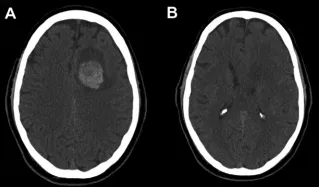

65岁男性患者因持续性头痛、眩晕24小时前往当地医院就诊。患者无慢性疾病史,未服用任何药物,基础血液检查结果正常。增强CT扫描显示左侧额上回区域存在与硬脑膜相连的类圆形病灶,病灶内部可见出血征象。

患者入院约6小时后病情急剧恶化,在转诊至上级神经外科中心途中突发意识丧失。紧急抢救后生命体征趋于稳定,抵达后立即进行CT复查,结果显示原病灶周围出现大量脑实质内出血及脑室内出血,确诊为良性脑膜瘤相关的"两阶段"复发性出血事件。